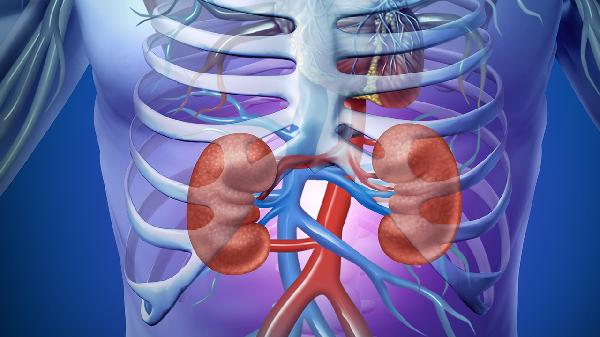

肾结石怎么形成

肾结石的形成可能与代谢异常、尿路梗阻、尿路感染、药物因素以及饮食因素等原因有关。

一、代谢异常

代谢异常是肾结石形成的常见原因之一。体内钙、草酸、尿酸等物质代谢紊乱,导致尿液中这些成分的浓度升高,从而析出结晶并逐渐聚集形成结石。高钙尿症、高草酸尿症等代谢疾病会使尿液中的成石物质过饱和,促进晶体形成和生长。患者可能出现腰部钝痛、血尿等症状。治疗时需针对原发代谢疾病进行干预,医生可能建议使用枸橼酸氢钾钠颗粒、别嘌醇片或氢氯噻嗪片等药物调节代谢,并配合饮食控制减少成石物质摄入。

二、尿路梗阻

尿路梗阻会导致尿液排出不畅,尿液在肾盂或输尿管内滞留,使得其中的矿物质浓度增加,易于结晶沉淀形成结石。梗阻可能由先天性输尿管狭窄、前列腺增生或肿瘤压迫等因素引起。患者常伴有肾积水、剧烈腰痛及排尿困难等症状。解除梗阻是治疗关键,医生会根据情况使用坦索罗辛胶囊、非那雄胺片等药物缓解症状,必要时通过手术去除梗阻原因,并鼓励患者增加水分摄入以稀释尿液。

三、尿路感染

尿路感染时某些细菌如变形杆菌能分解尿素产生氨,使尿液碱化,促进磷酸盐沉积形成感染性结石。反复感染会破坏尿路上皮,为晶体附着提供条件。患者可能出现发热、尿频、尿急及脓尿等表现。治疗需使用敏感抗生素如左氧氟沙星片、头孢克肟分散片或呋喃妥因肠溶片控制感染,同时多饮水冲刷尿道,减少细菌滋生。

四、药物因素

长期使用某些药物可能增加肾结石风险。例如过量服用维生素C补充剂可能增加尿草酸排泄,使用糖皮质激素可能影响钙代谢,某些抗HIV药物如茚地那韦也会诱发结晶形成。药物成分或其代谢产物在尿液中溶解度降低时易析出形成结石。患者服药期间可能出现无症状结晶尿或突发肾绞痛。建议在医生指导下调整用药方案,必要时换用替代药物,并定期监测尿液成分变化。

五、饮食因素

饮食中高嘌呤、高草酸或高钠食物摄入过多,同时水分摄入不足,会使尿液浓缩,成石物质浓度增高而促进结石形成。经常食用动物内脏、菠菜、巧克力等高草酸或高嘌呤食物,且每日饮水量不足,会增加尿酸结石或草酸钙结石概率。患者可能仅有轻微腰部不适或体检时偶然发现结石。调整饮食结构,限制成石食物摄入,增加水果蔬菜等碱性食物,保证每日充足饮水是有效的预防措施。

预防肾结石需要养成良好生活习惯,每日饮水至少2000毫升以保持尿液稀释,减少高草酸食物如菠菜、高嘌呤食物如海鲜摄入,适当控制钠盐和蛋白质摄入量。定期进行尿液检查和泌尿系统超声筛查,及时发现早期病变。保持适度运动有助于小结石排出,但应避免突然剧烈运动。出现疑似结石症状时应尽早就医检查,明确诊断后接受规范治疗。饮食调整结合医疗干预能有效降低结石复发风险。